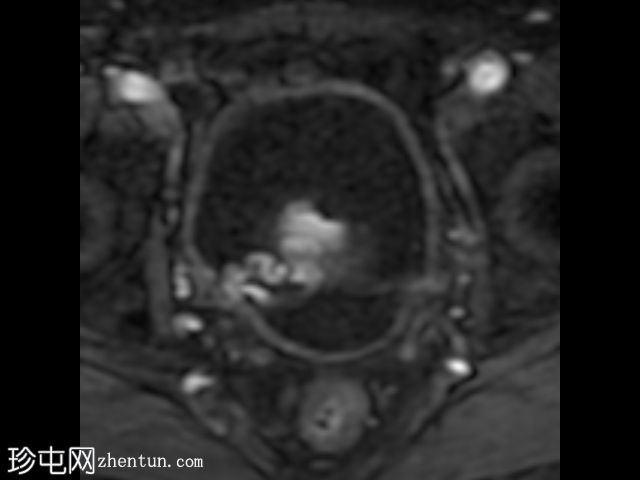

在T1和T2加权像上,于膀胱底部及右下外侧面偶然发现一处呈蛇形缠绕状的低信号区。动态序列中可见快速对比增强,提示所有影像学表现均源于血管,信号缺失与动静脉畸形有关,该畸形至少由膀胱下动脉供血,并由同侧局部扩张的静脉回流。

这些影像学表现符合局限性动静脉畸形,这种情况极为罕见。通常情况下,该畸形伴有肉眼血尿,但本例患者未出现此症状。通常情况下,该畸形由髂内动脉的多条供血动脉供血,血管造影被认为是确诊的金标准。